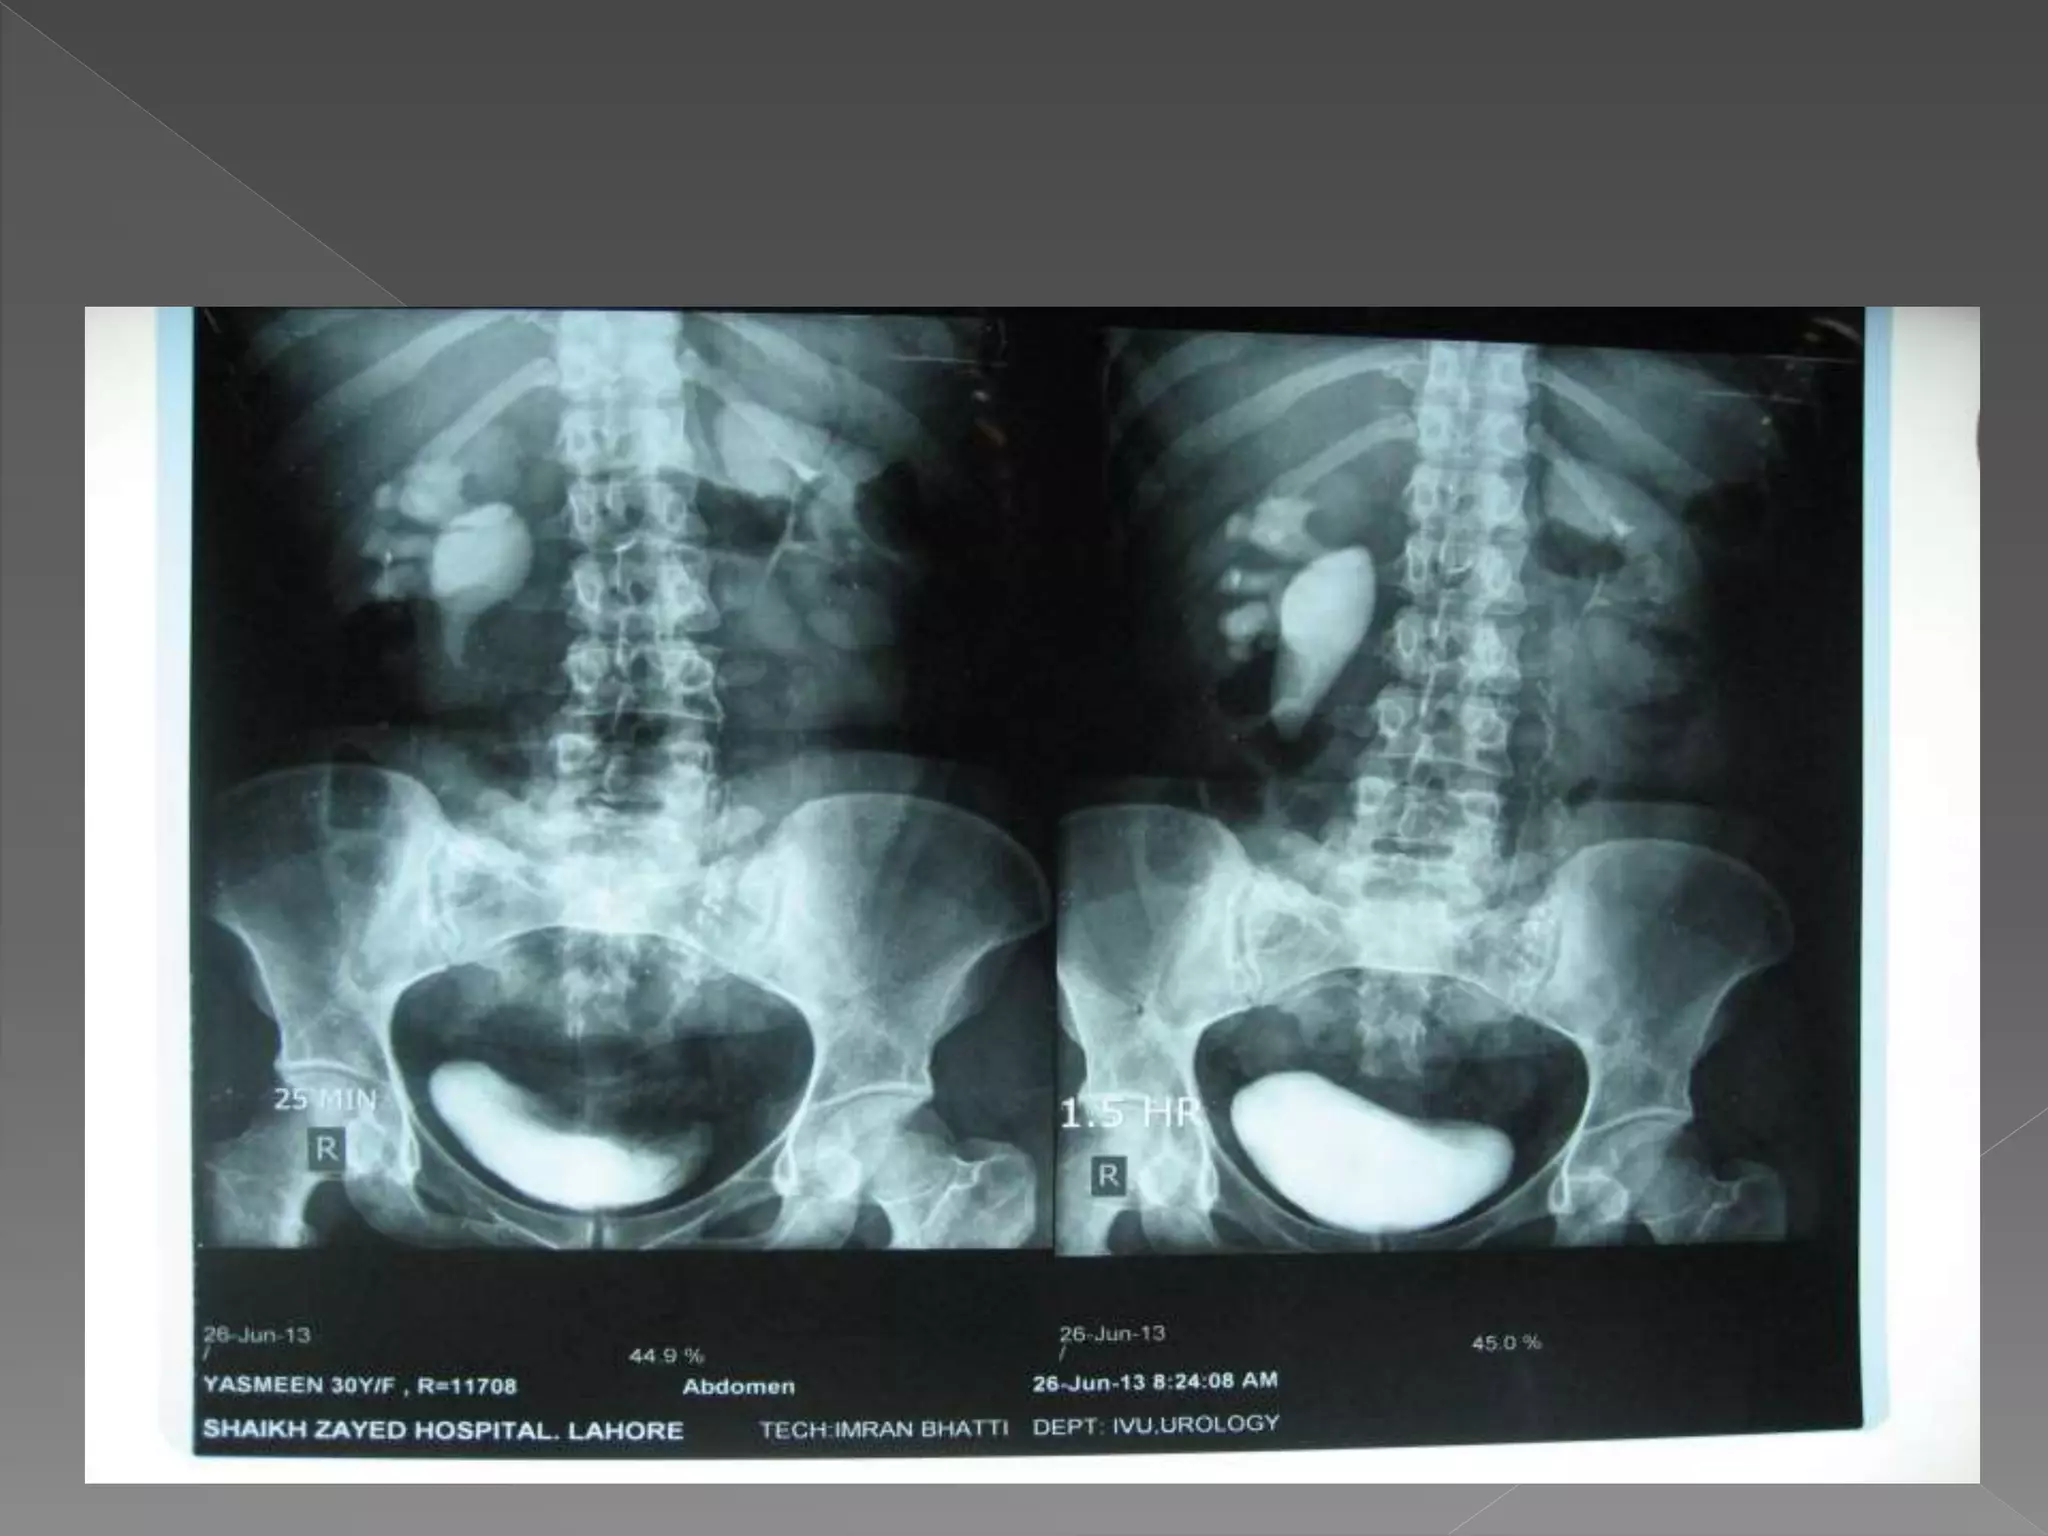

 On releasing compression increase flow in

ureters making them prominent in post

release film.

3) 25 mins

4) Post void